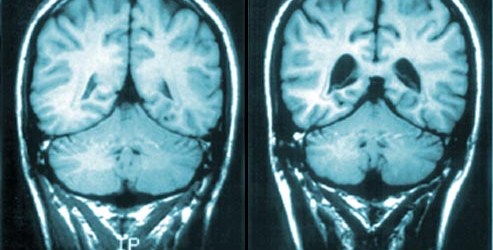

Here’s a TED Talk regarding schizophrenia that we didn’t have a chance to view in class the other day. It’s not often that you hear someone suffering with the disorder be able to speak so publicly about it.